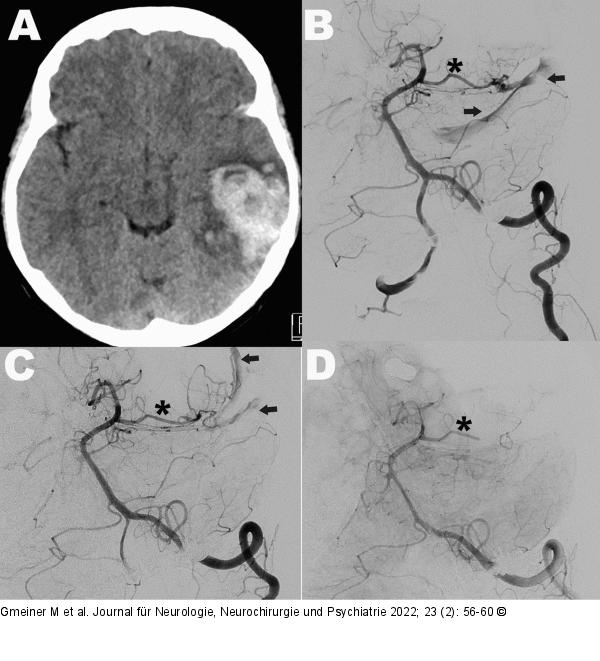

Abbildung 5: Piale arteriovenöse Fistel Piale arteriovenöse Fistel: A, B: Hämatom links temporal (Schädel CT, A) bei pialer arteriovenöser Fistel gespeist über die A. cerebri posterior (Stern) mit venöser Drainage in den Sinus transversus (Pfeil, präoperative Angiographie, B). C: In der intraoperativen Angiographie zeigt sich eine residuale Fistelbildung mit geänderter venöser Drainage (Pfeil). D: Die zweite intraoperative Angiographie bestätigt einen vollständigen Fistelverschluss. |

Piale arteriovenöse Fistel: A, B: Hämatom links temporal (Schädel CT, A) bei pialer arteriovenöser Fistel gespeist über die A. cerebri posterior (Stern) mit venöser Drainage in den Sinus transversus (Pfeil, präoperative Angiographie, B). C: In der intraoperativen Angiographie zeigt sich eine residuale Fistelbildung mit geänderter venöser Drainage (Pfeil). D: Die zweite intraoperative Angiographie bestätigt einen vollständigen Fistelverschluss. |